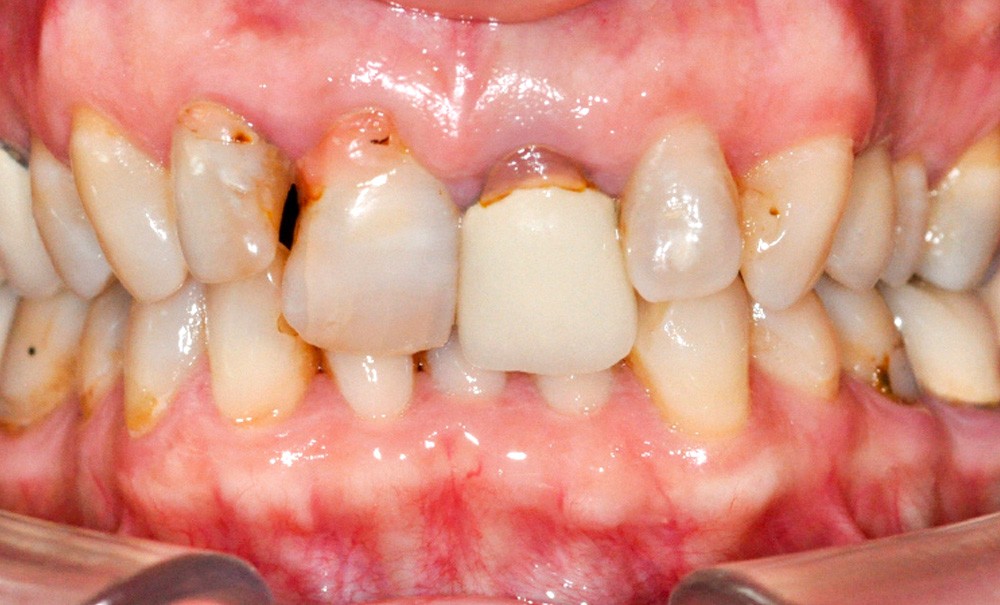

Mme Maryse D., âgée de 64 ans, se présente en consultation avec une forte demande d’amélioration esthétique de son sourire. La patiente est en bon état de santé général et non fumeuse.

Elle présente une ligne du sourire haute et découvre largement le parodonte lors d’un sourire forcé [1, 2], ce qui augmente le niveau d’exigence esthétique de la future restauration.

L’analyse du parodonte montre un biotype fin associé à quelques récessions modérées.

L’examen occlusal montre une classe II div 2 subdivision droite avec une forte linguo-version des deux incisives centrales maxillaires et, par voie de conséquence, des quatre incisives mandibulaires. La téléradiographie de profil met en évidence une typologie normodivergente sans décalage squelettique. La dimension verticale est correcte et la patiente ne souffre d’aucune dysfonction articulaire.

L’examen dentaire clinique et radiologique montre la présence d’une couronne avec tenon radiculaire sur la 21. On remarque une infiltration bactérienne radiculaire qui nécessiterait une intervention, mais le faible pronostic mécanique de la dent oriente plutôt vers son extraction. L’incisive centrale 11 présente une récession gingivale disto-vestibulaire maquillée par une fausse gencive rose en résine, jugée disgracieuse. Les collets entre les deux incisives centrales ne sont pas symétriques. Les incisives latérales sont en légère rotation et sont porteuses d’anciennes et volumineuses restaurations en composite qui participent à l’inconfort esthétique de la…